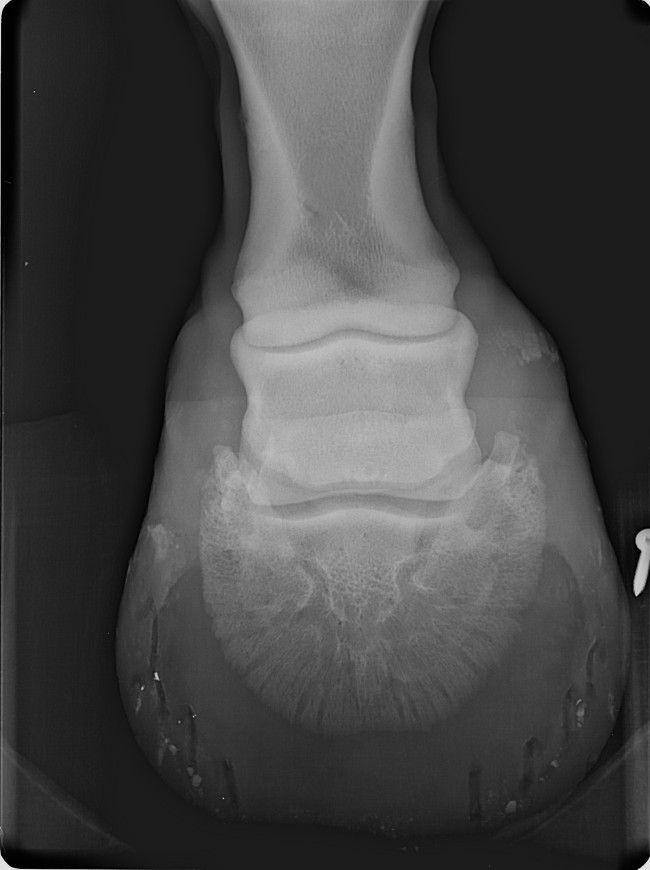

| Dire merci | de toute façon parage naturel ou non j'aurais eu ce soucis, peut être un an plus tard voir plus... Ca a juste accélérer le problème. Il a en plus une ostéite. Sinon le véto a fait exactement ce que mon véto a fait... Sauf qu'il a un oeil d'expert et pas de généraliste. Pour la "tendinite", (le tendon frottait un os qui pour finir l' abrasait ) qui est du au talon bas. Don on a fait 4 radios du pieds. On lui donne un anti inflammatoire pendant une semaine. Il a des fers à l'envers aux antérieurs. Et 6 mois de box avec sorti de 10 min par jour pendant un mois puis on rallonge de 5 min chaque semaine... Je retourne à la clinique fin septembre début octobre. |

| Dire merci | ![]() ![]() c'est le pied gauche ![]() le pied droit |